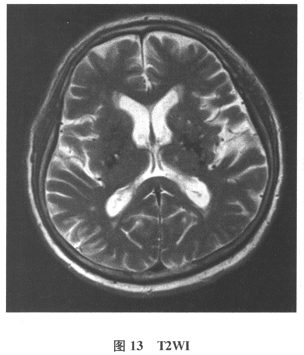

患者男,61岁。因“发作性头晕2年,加重伴记忆力下降、走路不稳3月余”就诊。查体:BP140/70mmHg;意识清楚,构音障碍,近期记忆力及远期记忆力均减退,以远期为主,计算力、理解力、定向力粗测正常。影像学检查见图13~图17。     临床上,用于观察白质疏松的最佳序列是()

A.T2WI

B.TIWI

C.FLAIR

D.DWI

E.GRE